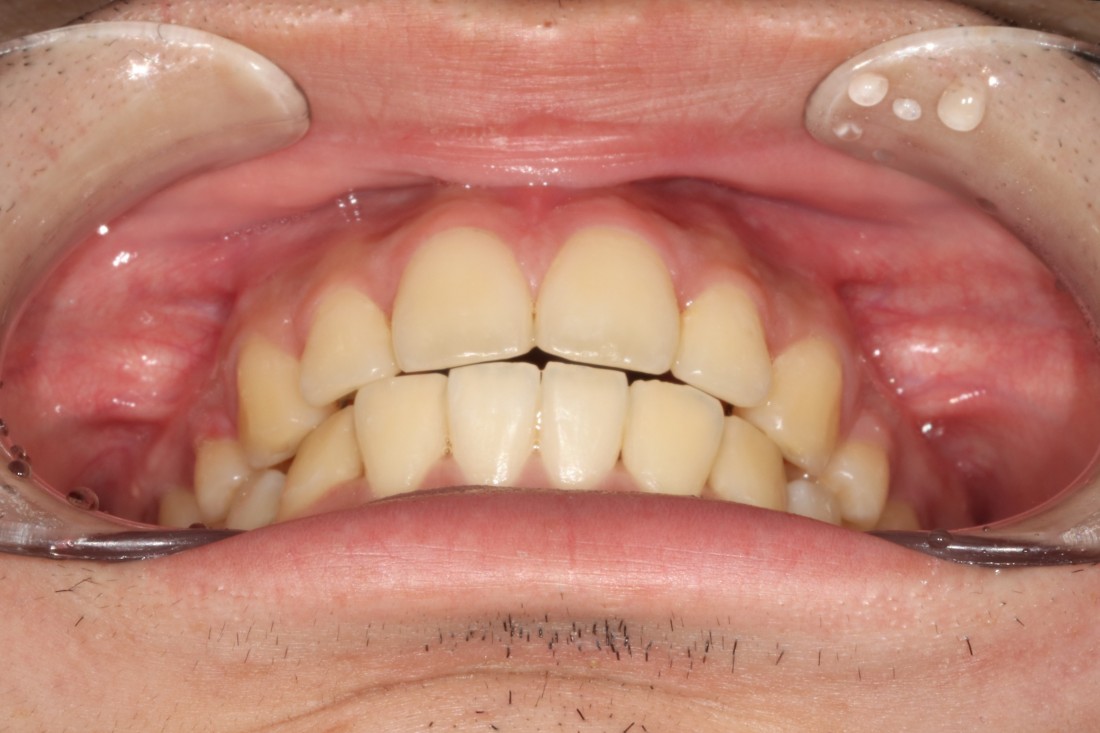

수많은 개방교합 교정 케이스를 보유하고 있으며,

교정 전/후 사진을 다양하게

홈페이지에 공유해드리고 있으니

광주 개방교합 치과의 실력을 믿으셔도 좋습니다.

광주 개방교합 치과에서는

개방교합 치료 후기 뿐만 아니라,

다양한 성인부정교합 교정 케이스를

투명하게 공개하고 있습니다.

수 백가지가 넘는 교정케이스를

다양하게 공유해드리고 있기 때문에

실력 면에서는 믿고 맡겨주셔도 좋습니다.